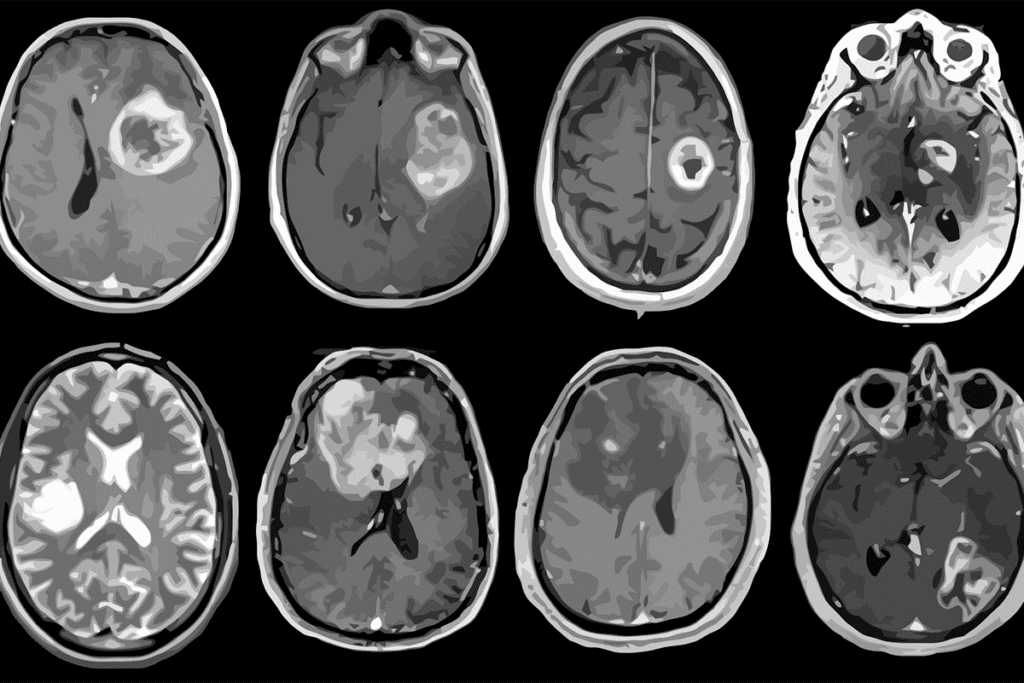

Imaging Tests for Brain Tumor Detection

Imaging tests are key in finding brain tumors. The main ones used are:

- Magnetic Resonance Imaging (MRI): MRI gives detailed brain images. It helps find the tumor’s size and how it affects nearby areas.

- Computed Tomography (CT) Scan: CT scans are fast and useful in emergencies. They show if there’s a tumor and if there’s bleeding or calcification.

- Positron Emission Tomography (PET) Scan: PET scans help tell tumor types and check metabolic activity. This helps plan treatment.